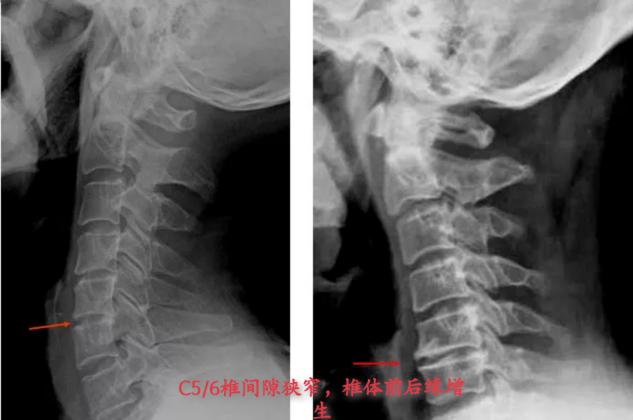

1.骨关节损变型:

病因主要是骨质增生、椎间盘变性、椎小关节炎。

从X光片可看到骨质增生侵入椎管、椎间孔、横突孔;椎间隙变窄等。与临床症状的定位相一致。

骨关节触诊是正常的。

治疗上可以使用牵引疗法,很快就能使症状得到缓解。